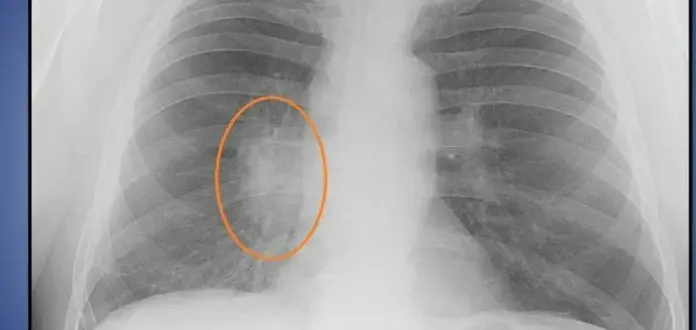

Затемнение в лёгких: что это такое и когда стоит беспокоиться?

Когда врач смотрит рентгеновский снимок легких и замечает затемнение, это еще не повод для паники, но и не тот случай, когда можно просто забыть о результатах обследования. Затемнение — это признак, который может указывать на совершенно разные состояния: от безобидных особенностей строения до серьезных патологий.

Почему на снимке появляется затемнение

Рентген работает по простому принципу: чем...